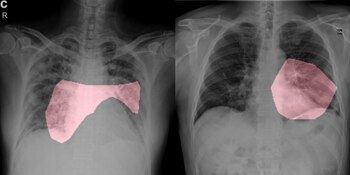

Cuando hoy una persona llega a un hospital con síntomas de neumonía grave, lo primero que quieren hacer los médicos es confirmar o descartar que tenga COVID-19. Pero el análisis lleva horas (hasta un día entero) y, mientras tanto, el paciente debe ser tratado como si tuviera el nuevo coronavirus, que es altamente contagioso. Para eso se consumen recursos que escasean: una cama de internación en cuarentena, equipo de protección para el personal de salud. Si hubiera otra manera de diagnosticarlo, se ahorraría todo eso, además de tiempo. Pero para el ojo humano la radiografía, el primer estudio que se indica, muestra imágenes muy parecidas: pulmones infiltrados de fluidos.

¿Qué pasaría si la inteligencia artificial (IA) pudiera interpretar las placas de rayos X mejor que la inteligencia de las personas? Una serie de trabajos científicos ha aplicado las redes neuronales (sistemas de computación que imitan la conexión biológica de neuronas) para la clasificación de radiografías, con la idea de que el aprendizaje profundo y el aprendizaje automático, que son particularmente buenos para el reconocimiento de imágenes, pueden distinguir el daño que el COVID-19 hace a los pulmones del que provoca la neumonía común.